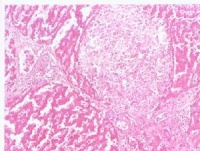

本病可因胃壁坏死发生急性胃穿孔急性腹膜炎

急性胃扩张可因胃壁坏死发生急性胃穿孔和急性腹膜炎